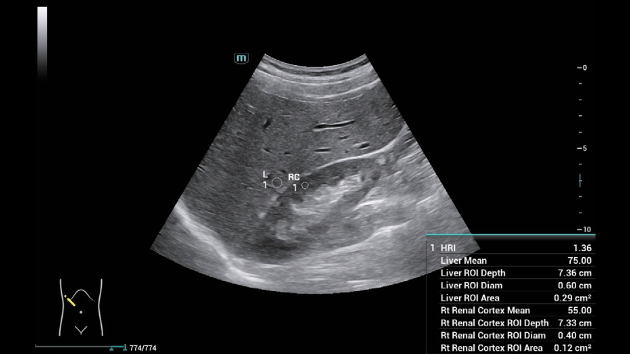

A linha Consona apresenta solu??es inovadoras e eficientes que o ajudam a realizar diagnÃģsticos em diversos tipos de pacientes.

N?o importa se sua rotina ÃĐ em hospitais, clÃnicas ou se vocÊ estÃĄ aprimorando habilidades em Imagem Geral, SaÚde da Mulher ou na ÃĄrea Cardiovascular; vocÊ encontrarÃĄ ferramentas altamente poderosas disponÃveis para manter-se na vanguarda.

Solu??es abrangentes de imagens com tecnologia ZST+

A plataforma ZST+ ÃĐ uma inova??o extraordinÃĄria, representando a evolu??o do ultrassom. Transformando as mÃĐtricas de ultrassom: da forma??o convencional do feixe ao processamento baseado em dados de canais. Supera a limita??o de compensa??o tradicional entre resolu??o espacial, resolu??o temporal e uniformidade de tecido, oferecendo qualidade de imagem excepcional para solu??es de imagem infinitas com melhorias inigualÃĄveis.